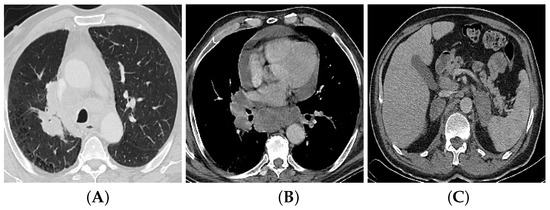

4. Imaging and Lung Cancer TNM Staging

4.1. T (Tumor) Descriptor

4.3. M (Metastasis) Descriptor